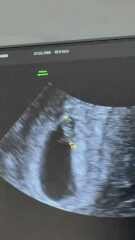

Just for fun really as I know it’s 50/50 but anybody any good at guessing this haha? Transvaginal scan. 7 weeks 5 days but measuring 6 weeks 6 days at the time of the scan 🤍 thank you xx